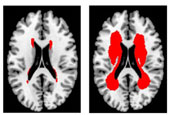

• 65~74세 뇌경색 환자의 대뇌부챗살(운동•감각신경이 지나는 대뇌 중앙 부위) MRI 사진

한국 연구진이 최근 뇌경색의 위험 정도를 객관적으로 알 수 있는 '허혈 뇌지도'를 세계 최초로 개발했다.뇌경색은 뇌혈관이 괴사되는 질병으로 2013년 암에 이어 한국인의 질병으로 인한 사망 가운데 두 번째로 높은 뇌졸중의 주요 발병 원인이다. 지금까지는 자기공명영상(MRI) 검사로 의사가 환자의 뇌손상 정도를 주관적으로 판단해 뇌경색에 대한 진단을 해 왔으나 이번에 개발된 '허혈 뇌지도'로 객관적으로 그 위험성을 진단 할 수 있게 됐다.한국표준과학연구원과 동국대 일산병원 등 전국 11개 대학병원으로 구성된 공동연구팀은 뇌경색 환자들이 공통적으로 뇌에 만성 허혈(혈관에 문제가 생겨 혈류가 막히거나 피가 부족한 상태) 증세를 보이는 점에 착안, 연구에 들어갔다. 이들은 지난 5년간 국내 11개 대학병원에 입원한 뇌경색 환자 2,699명의 MRI 촬영 사진 6만 여장을 분석했다. 환자 별 나이, 체중, 혈압 등의 700가지 데이터 정보를 분석하고 연령대별 환자의 뇌경색 정도를 100등급으로 분류했다.이렇게 만들어진 ;허혈 뇌지도;는 뇌경색 위험 정도를 객관적인 도표로 보여준다. 뇌경색 정도가 심할수록 등급 숫자가 높아지는 ;허혈 뇌지도;는 연령대별 도표가 제공돼 ;뇌 건강나이;도 확인할 수 있다.▲ 65~74세 뇌경색 환자의 대뇌부챗살(운동;감각신경이 지나는 대뇌 중앙 부위) MRI 사진의 등급별 비교: 1등급(왼쪽)의 경우 혈관 손상이 거의 보이지 않으며, 50등급(가운데)은 중앙혈관 일부에 손상이 보이고 100등급(오른쪽)은 중앙 혈관 상당부분이 손상됐음을 알 수 있다. 사진 붉은색 부분이 손상된 뇌 혈관.▲ ;한국인 허혈 뇌지도; 표준도판과 환자의 MRI 사진을 비교해 뇌경색 정도를 파악 할 수 있다.▲ 김동억 교수연구책임자인 김동억 한국인 뇌MR영상 데이터센터장은 ;뇌경색은 사망률과 장애율이 매우 높은 병이기 때문에, 예방이 무엇보다 중요하다;며 "만성 허혈성 뇌손상은 증상이 없는 사람의 MRI에서도 흔히 관찰되며 뇌경색의 발생 위험도를 잘 반영한다"며 ;한국인 허혈 뇌지도가 병의원에서 많이 활용될 수 있을 것으로 기대한다;고 말했다.연구팀은 한국인 허혈 뇌지도를 ;한국인 뇌MR영상 데이터 센터 홈페이지(http://brainmr.com)에 공개하고 누구나 다운로드 받을수 있도록 했다. 또한 모든 병원을 대상으로 진료실 비치용 패널로 제작;배포할 계획이다.;뇌경색 지도; 연구 성과는 미국뇌졸중학회 학술지 ;스트로크; (Stroke) 12월호에 게재됐다.▲ 뇌경색 지도 연구 성과는 미국뇌졸중학회 학술지 ;스트로크; (Stroke) 12월호에 실렸다.윤소정 코리아넷 기자자료 동국대학교 일산병원arete@korea.kr▲ 한국표준과학연구원이 한국의 11개 대학병원과 공동 개발한 ;한국인 허혈 뇌지도;를 의료용 참조표준도판으로 만든 모습. 환자의 MRI사진과 비교하면 뇌경색 위험 정도를 알 수 있다. 2015.01.02